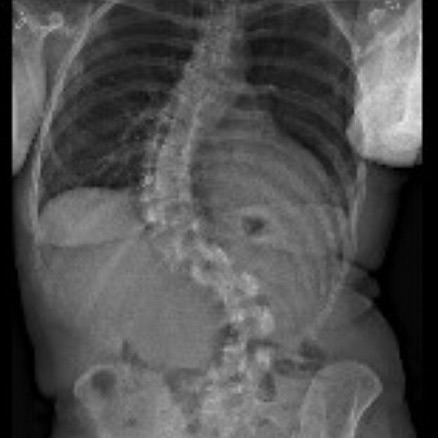

At my 3-month post-op appointment, my surgeon lifted all my restrictions and said I can return to all activity, “just listen to [my] body.” She measured my X-rays (above) and said my lumbar curve decreased 20 degrees, and the thoracic is the same. Also, I grew half an inch. I showed her the scoliosis program I found in New Hampshire, and she was all for it. I’ve booked a furnished apartment in New Hampshire 4/20-5/31 and scheduled the 12 sessions of treatment at the PT clinic there. I’m hopeful that will help with my back pain, and maybe even reduce my thoracic curve. And right before that, I’ll be attending Bionicon!

I’m walking without the cane and my balance feels back to how it was pre-surgery. My hip pain is still gone, but my low-back pain is where it was pre-surgery. The pain in my ribs is still intense. I wake up with my pain at a 4-5 and by the end of the day it’s an 8-9. The pain matches the compression you can see from these pics (morning on the left, bedtime on the right).